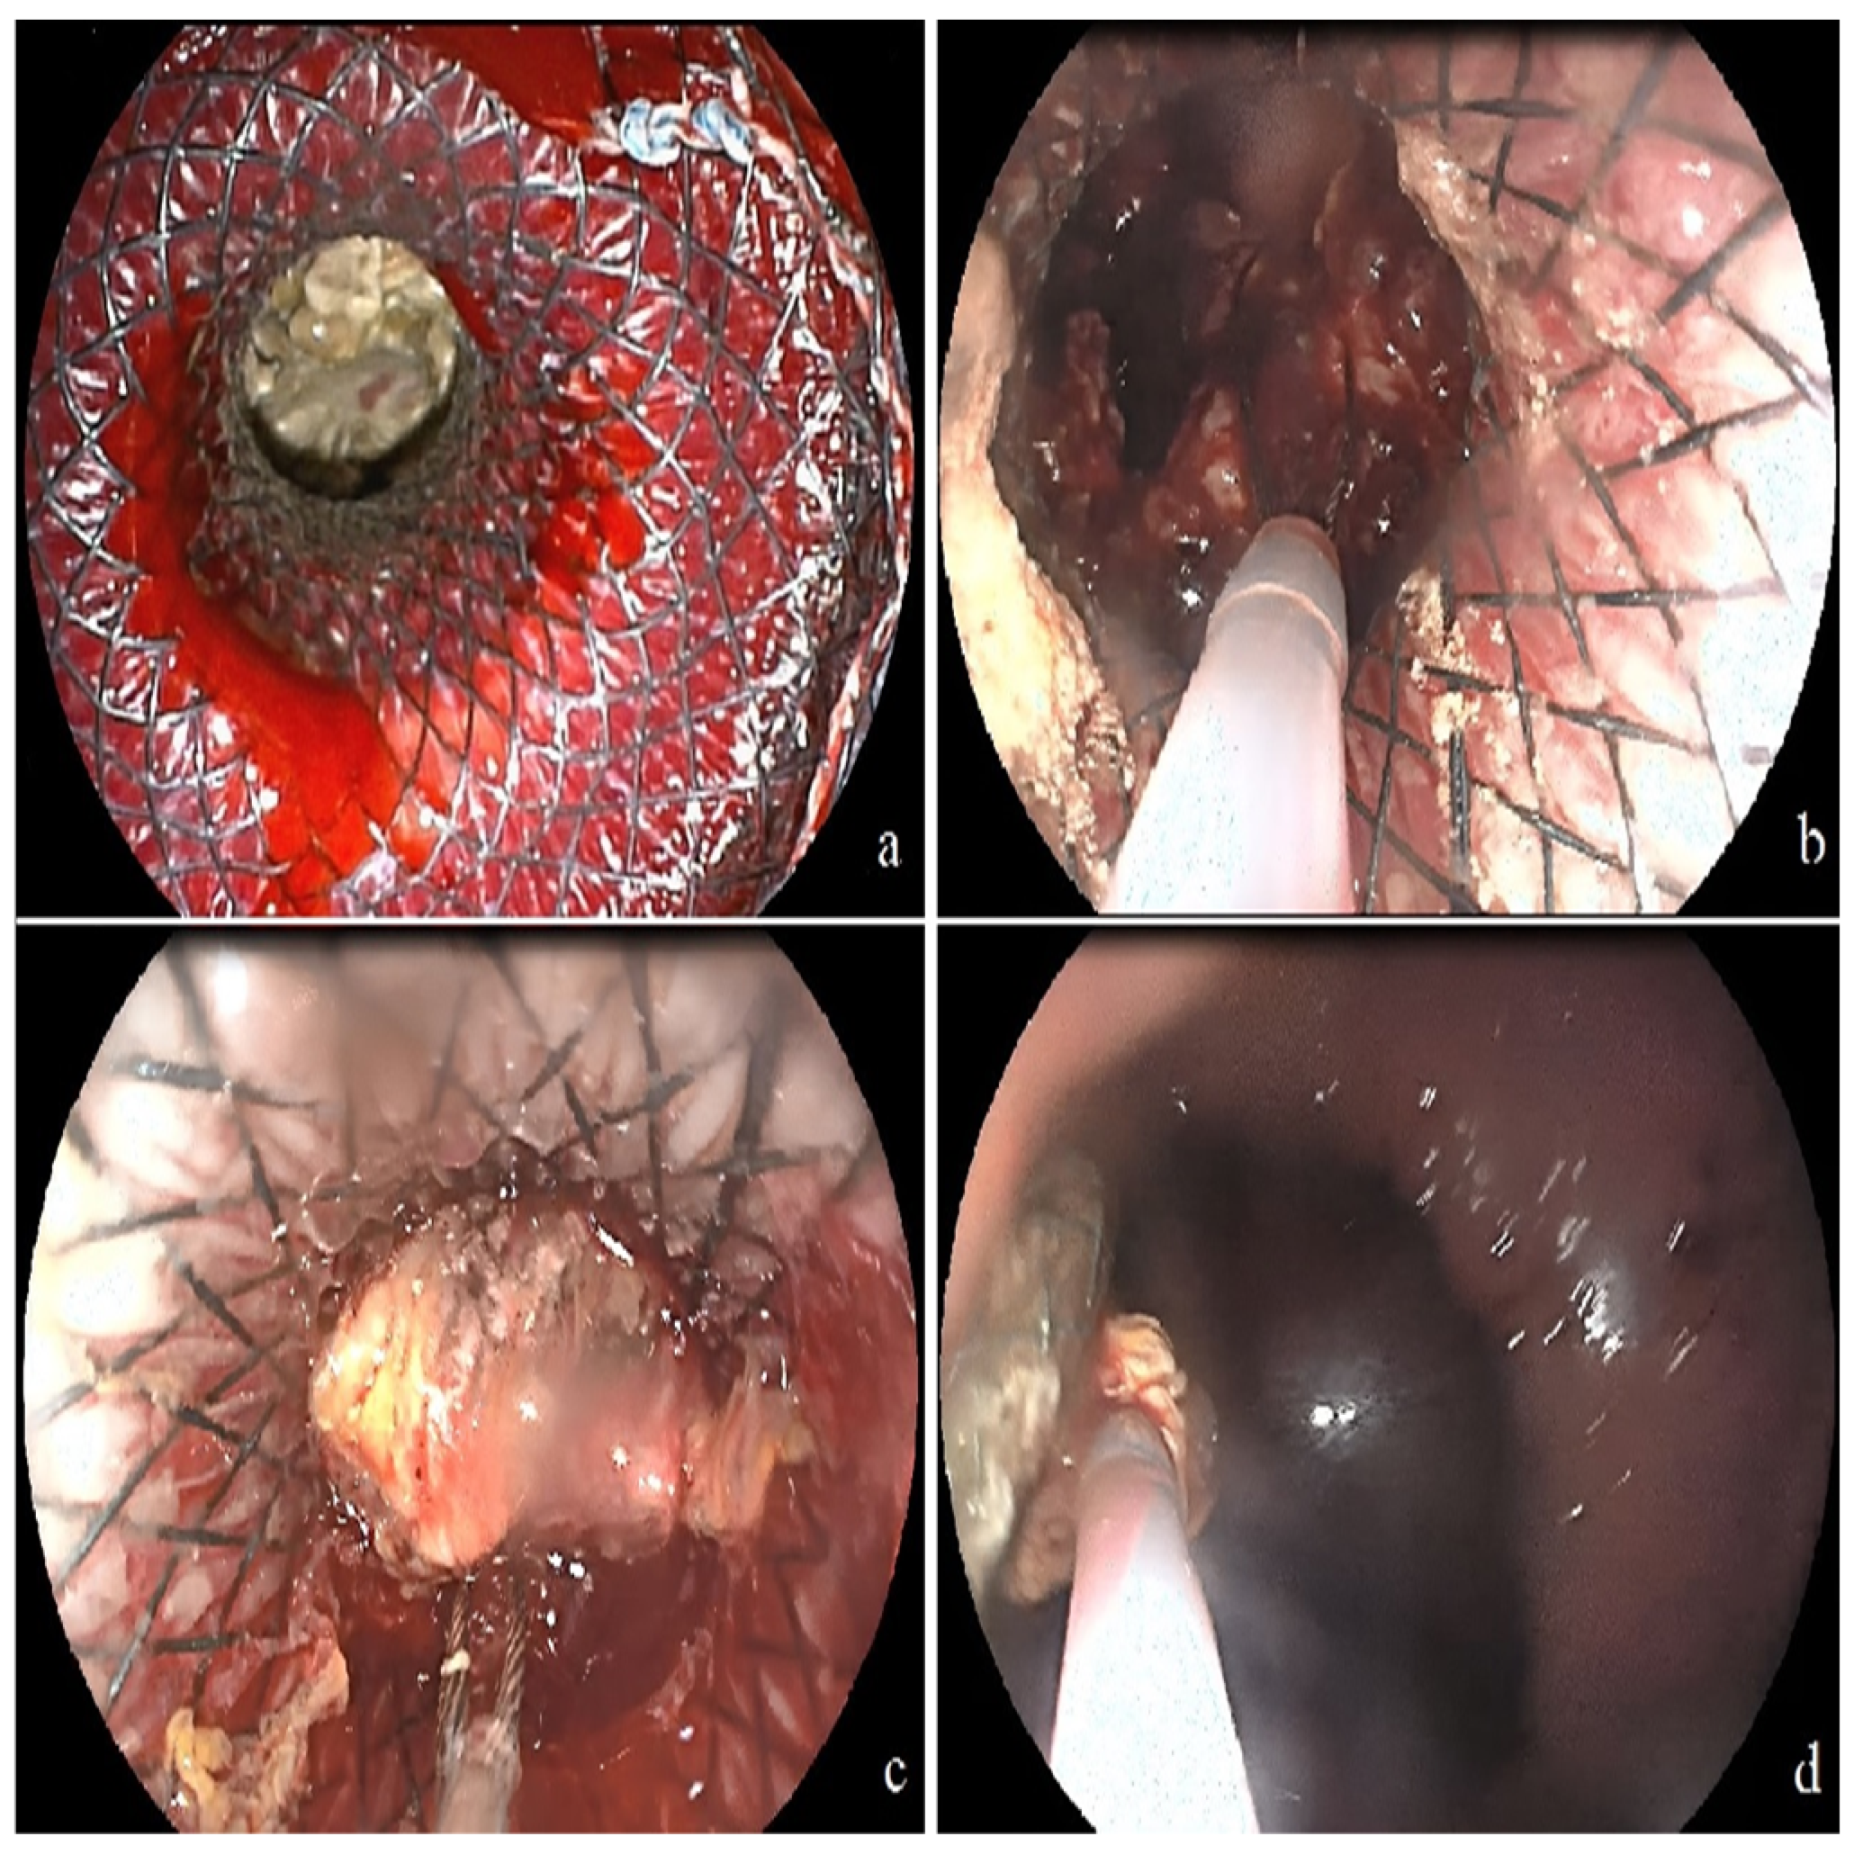

| Direct endoscopic necrosectomy needed | 7 (63.6) |